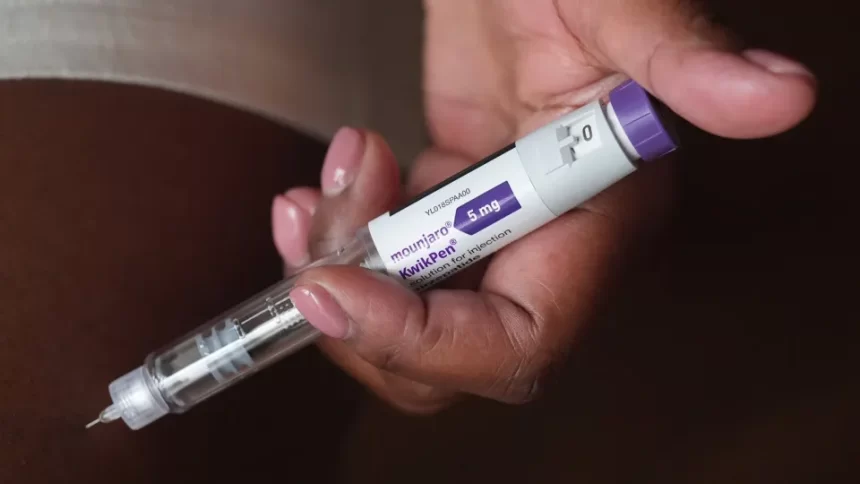

SÃO PAULO, SP (FOLHAPRESS) – A Anvisa (Agência Nacional de Vigilância Sanitária) aprovou na quarta-feira (18) o registro da versão multidose do Mounjaro, medicamento à base de tirzepatida indicado para o tratamento de diabetes tipo 2 e para o controle do peso em pessoas com obesidade ou sobrepeso.

A nova apresentação, fabricada pelo laboratório americano Eli Lilly, diferentemente das canetas descartáveis já disponíveis no mercado, utiliza uma versão reutilizável, que permite múltiplas aplicações a partir de um mesmo frasco. A receita médica é obrigatória para a compra e ainda não há uma estimativa de valor no Brasil.

O tratamento com o Mounjaro funciona em doses semanais, com quatro aplicações por mês. “Anteriormente, quando se comprava o Mounjaro, tinham quatro canetas, cada uma com uma dose única de aplicação”, explica Felipe Henning Gaia Duarte, endocrinologista e presidente da Sbem-SP (Sociedade Brasileira de Endocrinologia e Metabologia regional de São Paulo). “Essa caneta atual vem com as quatro doses dentro e você regula cada dose para aplicar, durando o mês inteiro.”

A versão multidose do mounjaro chega em seis concentrações: 4,17 mg/ml, 8,33 mg/ml, 12,5 mg/ml, 16,7 mg/ml, 20,8 mg/ml e 25 mg/ml.

A aplicação é subcutânea, feita na camada de gordura sob a pele, e os efeitos colaterais mais comuns são gastrointestinais, como náusea, constipação, diarreia e vômito.